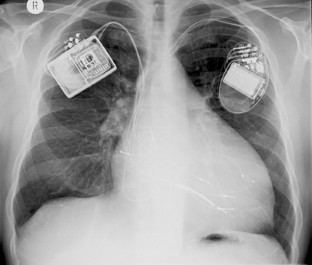

Die intermittierende Stimulationsabgabe erfolgt über 2 rechtsseptal transvenös platzierte Schraubelektroden, die mit der zusätzlichen Vorhofelektrode mit dem wiederaufladbaren Aggregat verbunden sind. Das Kontraktilitätsmodulationssystem verfügt weder über eine herkömmliche antibradykarde noch über eine antitachykarde Funktion.

Abb. 1